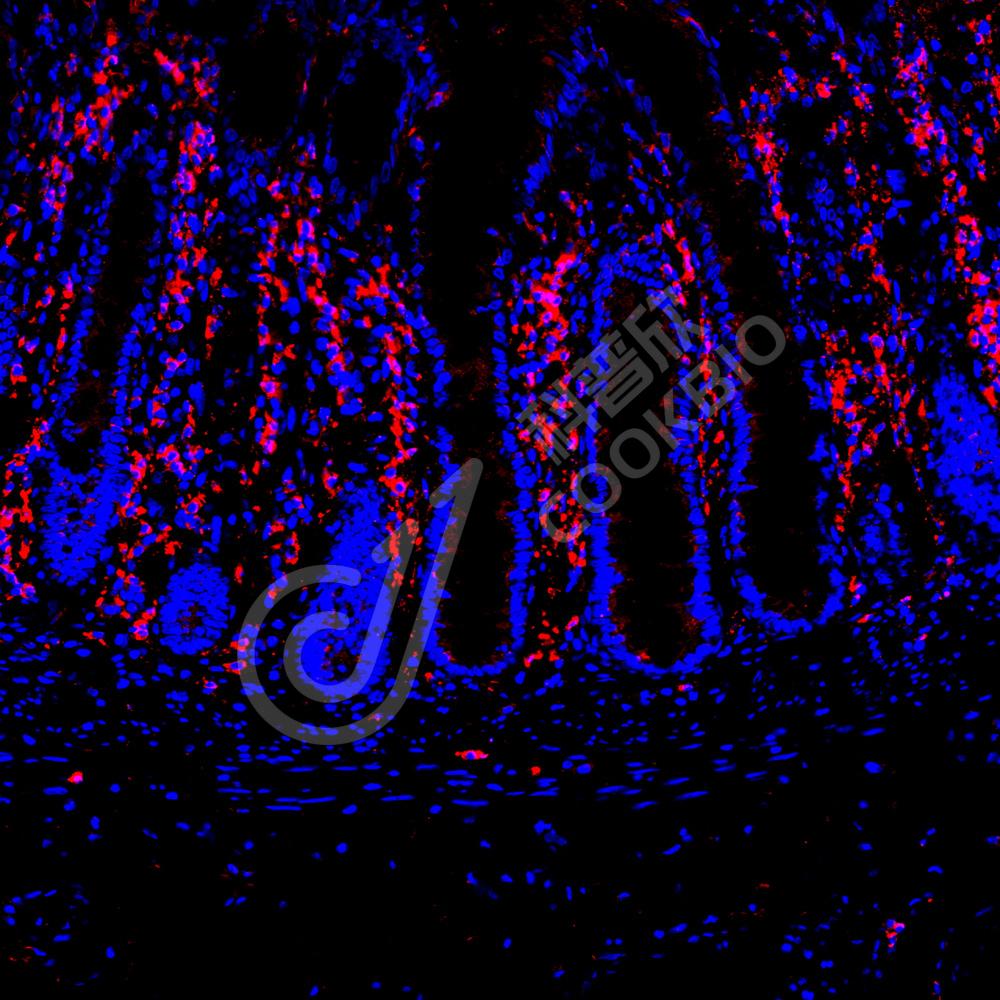

IF检测GRP94蛋白(货号 K135478)(红色).

样品: 人结肠, 4%多聚甲醛 (货号KSG1101) 固定12-24小时.

抗原修复: Tris-EDTA抗原修复液(pH 9.0) (KSG1203), 98℃, 20分钟.

封闭: 3% BSA(货号KSGC305010)的PBS溶液, 室温孵育30分钟.

—抗: 1: 1300稀释, 4℃ 孵育过夜.

二抗: Cy3标记山羊抗兔IgG (H+L) (货号KB63909), 1: 300稀释, 室温孵育1小时.